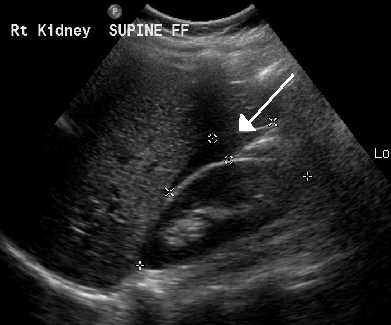

- 복강 내 액체: 직장자궁와에서 소량의 무에코성 액체는 자궁내 임신과 자궁외 임신 모두에서 흔히 발견된다.[5] 그러나 에코 발생성 액체(혈액 추정)는 자궁외 임신 여성의 28~56%에서 발견되며, 복강 내 혈종을 강력히 시사한다.[5] 이는 반드시 나팔관 파열이 아니며, 원위 나팔관 개구부 누출 결과일 수 있다.[5] 액체가 자궁저에 도달하거나 방광자궁와에 존재하면 의미있는 소견으로 간주된다.[5] 간신와에 액체가 보이면 심각한 복강 내 출혈의 표지자이다.[5]

- 복강천자: 질과 직장 사이 공간(더글라스와)에서 체액을 채취하여 내출혈 여부를 확인하는 덜 일반적인 검사. 혈액이 발견되면 파열된 자궁외 임신을 시사할 수 있다.

요약하면, 먼저 소변 hCG 검사로 임신을 확인한 후, 초음파 단층 촬영이나 복강경 검사로 자궁강 외 착상 여부를 진단한다. 유산이 발생하면 심한 하복부 통증, 더글라스와 압통, 복막 자극 증상을 보이며, 이는 초음파상 더글라스와 내 에코 프리 스페이스(무에코 공간)나 더글라스와 천자 시 혈액이 흡인되는 것으로 확인될 수 있다.